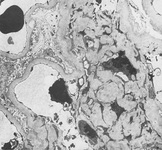

Doença renal diabética

Doença renal diabética: na posição de 12 horas - nódulos de Kimmelstiel-Wilson no início, uma forma arredondada de expansão mesangial

Do acervo do Dr. Raoul Fresco; usado com permissão